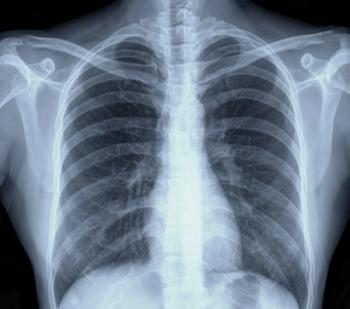

A new study in England shows a strong link between higher rates of chest x-ray referrals in general practice patients with symptoms, such as persistent cough, and earlier lung cancer diagnoses, along with improved outcomes.